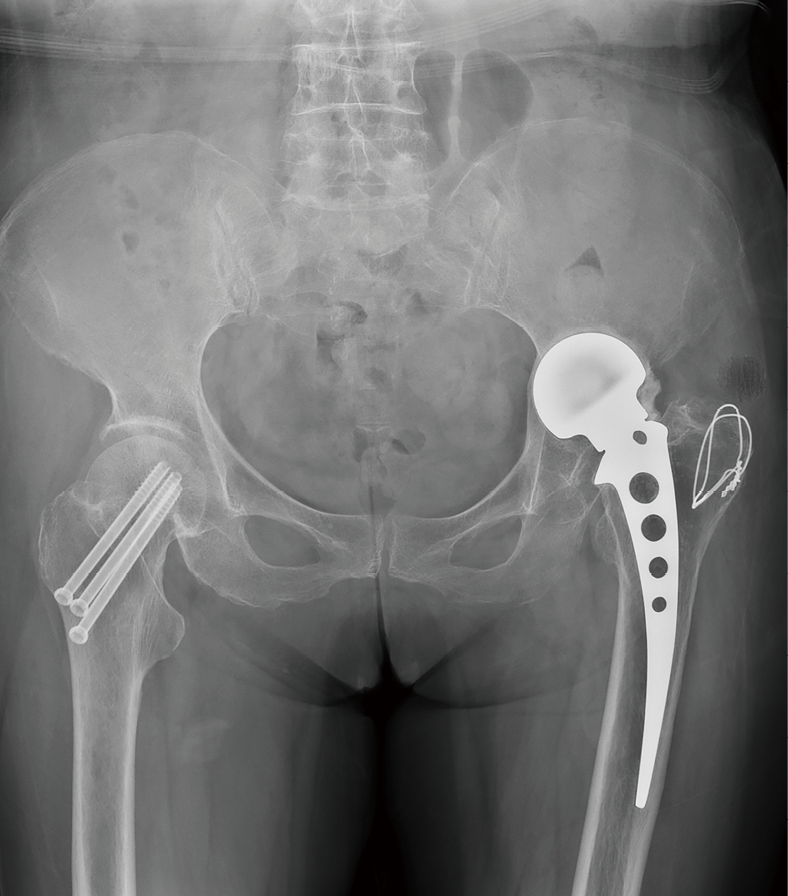

病例2:髋关节置换术后严重髋臼内陷, 使用3D打印垫块及组配柄完美重建